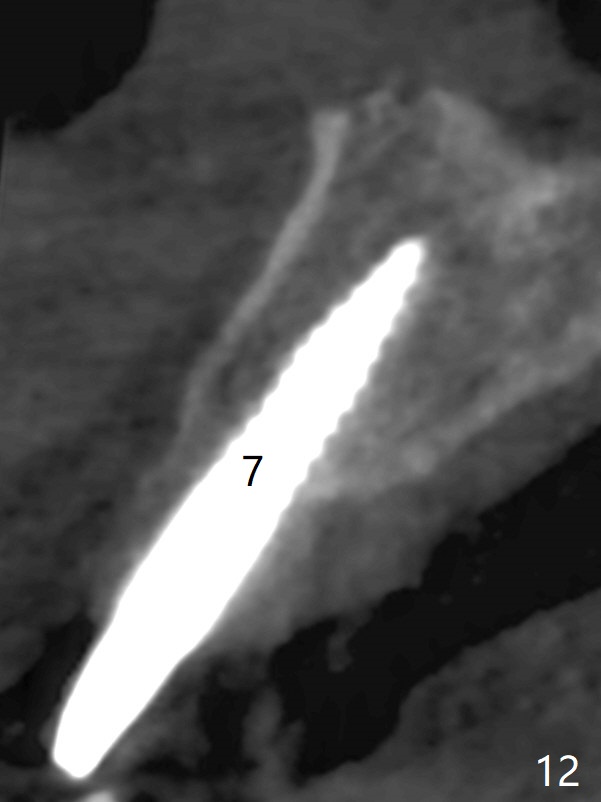

To have enough clearance for the splinted provisional at #6-12 (Fig.1 *), composite has been placed in the posterior teeth (bilateral, *, Fig.2). When the composite is removed, there is no clearance between the implants/abutments of #7 or 10 (Fig.3). Incision is made with removal of the 1-piece implant at #7; there is enough bone to move the osteotomy buccal (Fig.4 arrowhead). When the same implant is placed buccal (Fig.5), there is sufficient clearance for restoration (Fig.6 *), while there is still enough buccal bone left (Fig.7). When the patient returns 5.5 (for #7 and 10)/6.5 (#6,11,12) months postop, his chief complaint is tenderness lingual to #11. In fact, the abutment screw is loose at #11, while the implant at #10 has mobility (Fig.8), which is related to loss of the posterior stops (*) due to wear. There is slight bone loss mesial to #10 implant 5.5 months postop (Fig.10, as compared Fig.9). CBCT taken 5.5/6.5 months postop shows no bone loss (Fig.11-15). The 3x14 mm 1-piece implant at #10 is mobile 9 months postop and is removed and replaced by a 3.5x13 mm 2-piece one with slightly buccal osteotomy (Fig.16). PAs are taken prior to impression (Fig.17,18). The abutment at #12 is loose (<). More composite needs to be added to the occlusal surface of the upper posterior teeth. Finally the patient agrees to have crowns for the upper posterior teeth.